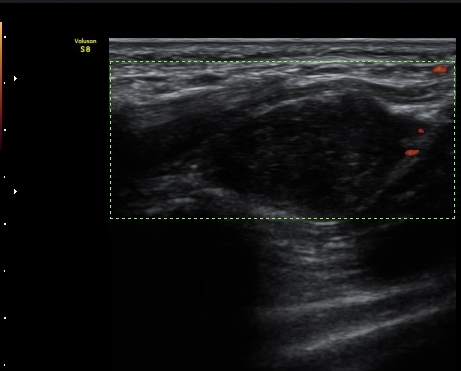

ŽÃËÀÚ¸¦ ¸»´ÜÀ¸·Î À̵¿ÇÏ´Ï °¥°í¸®»À ³»Ãø¿¡¼­ Ç¥Ãþ°¨°¢½Å°æ°ú ½ÉºÎ¿îµ¿½Å°æÀÌ °üÂûµÈ´Ù(»çÁø 3).